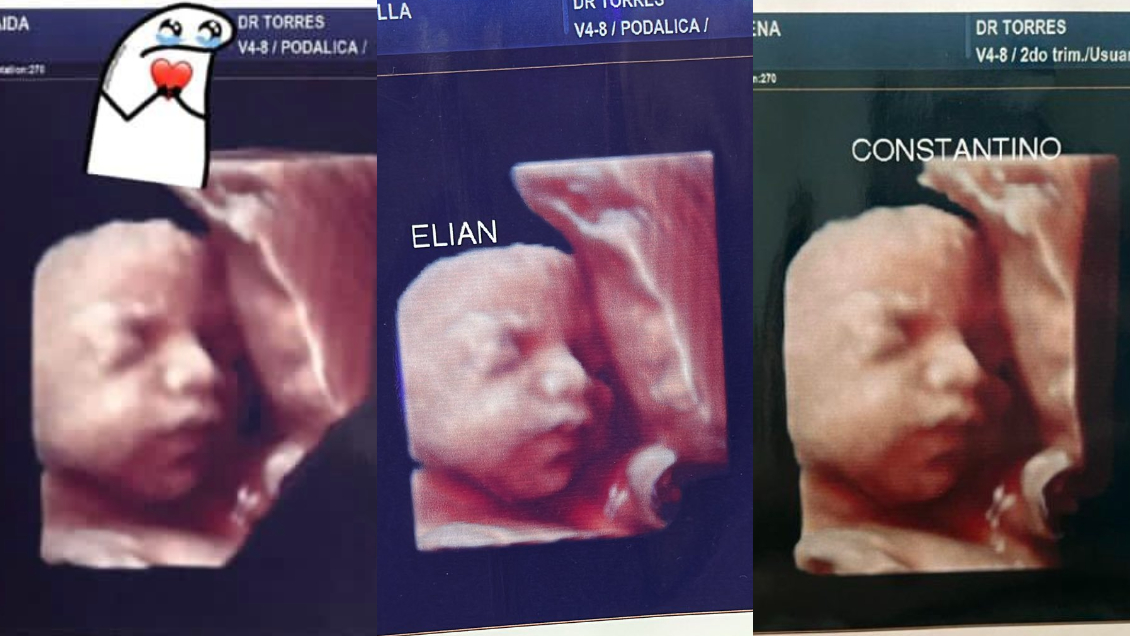

Un grupo de cuatro mujeres que se atendieron en la misma clínica denunciaron a través de redes sociales que les enviaron la misma imagen después de su ecografía.

Los hechos ocurrieron en una clínica privada de Formosa, en Argentina, donde ofrecían ecografías "5D".

Las cuatro mujeres descubrieron se dieron cuenta de la estafa cuando una de ellas compartió a través de TikTok la imagen de su "bebé".

"Ese no puede ser tu bebé (...) Tengo la misma imagen", le comentó una internauta, lo que encendió las alarmas.

"Por ahora somos 3 mamás a las que una clínica ESTAFÓ con una foto de un bebé que no es el nuestro. Está de más decir que encima que cobran carísimo uno se va ilusionado por ver a su bebé y tener un lindo recuerdo. Estamos en busca de más mamás con el mismo bebé", denunció otra mujer a través de Facebook.